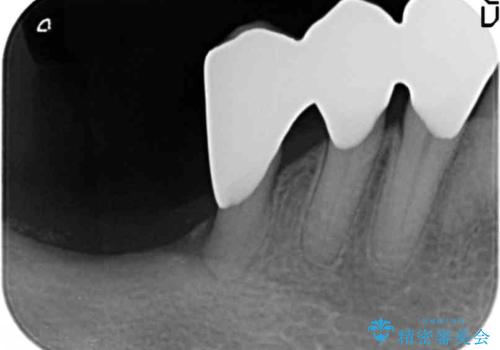

- 下の前歯(左下2)と奥歯の動揺がひどくなってきたことを主訴に来院された患者様です。

精査したところ、前歯の咬み合わせが反対になっていること、下の奥歯(下顎両側67)が4本欠損していることから動揺が生じていました。

入れ歯も抵抗があるとのことから、相談を重ね、今の状態では保存不可能な下の前歯(左下2)を抜去し、ブリッジや連結補綴により動揺を抑えることにしました。

また、咬み合わせが反対になっている上の前歯(左上2)も補綴で形を変えることにより、咬合を改善しました。

下顎大臼歯が欠損したままで今ある歯に負担がかかりやすいことから、長期的予後は保証できないことをご理解頂いた上で治療を行いました。

- ¥1,110,000 (根管治療×1本、土台×2本、仮歯×9本、クラウン×9本)費用は治療当時の料金となります